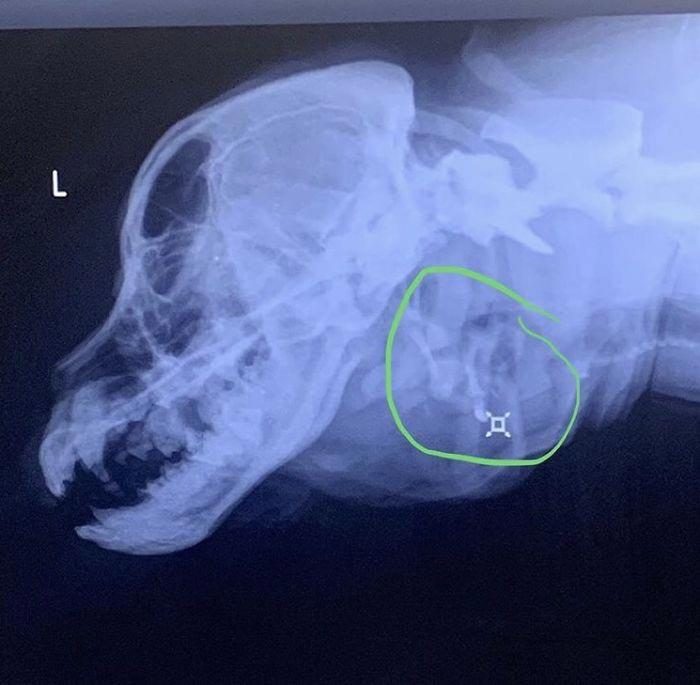

Зеленый кружок показывает ее лишнюю трахею, которая не полностью сформирована